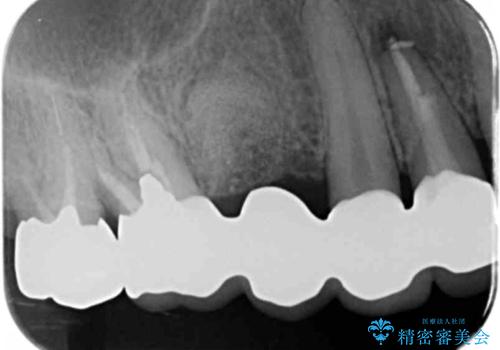

- 58.3万円(ジルコニアクラウン×4・仮歯×4・歯槽堤保存術)費用は治療当時の料金となります

ブリッジによる補綴を行うことで周囲の歯の噛み合わせも改善ししっかりと噛むことができるようになりました。